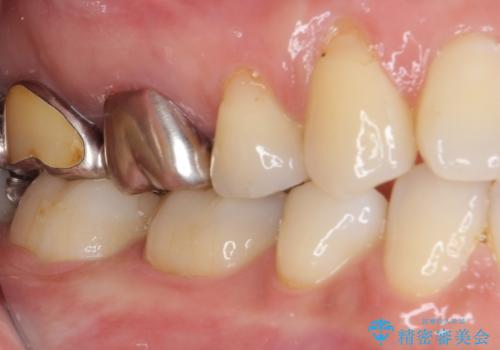

- 口を開けたときに目立ってしまう銀歯をセラミックに替えたいとのことで来院された患者様です。

上顎や親知らずにも銀歯がありましたが、今回の治療では目立つ下顎の銀歯4歯をセラミッククラウンやセラミックインレーに置き換えることにしました。

話をする度に相手の視線が銀歯に注がれている気がしているとのことでしたが、目立つ銀歯を自然な色合いに仕上げることができ、患者様には大変満足していただきました。